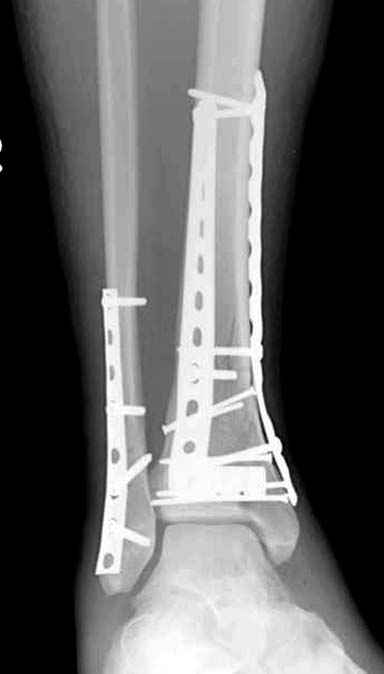

Спасибо за советы. Выполнен МОС обоих костей голени

По представленным послеоперационным снимкам создаётся впечатление сохраняющегося подвывиха + итраоперационно обнаруженный разрыв межкостной мембраны.

Извините за некачественные снимки и неправильную укладку в прямой проэкции. Подвывих рентгенологически не определяется. Кроме этого, после МОС малоберцовой кости интраоперационно однозубым крючком проверена стабильность синдесмоза - он стабилен. Кроме этого, интраоперационно проверена стабильность стопы в голеностопе - люфта ее при боковых отклонениях не определяется, также визуально при этом приеме отклонения малоберцовой кости кнаружи в ДМС не определяется. В дополнение к этому (у ассистента были сомнения) был сделан доступ к межберцовой связке и ее визуальный осмотр- она оказалась целой. При данных обстоятельствах позиционный винт мы не вводим.

Показания для остеосинтеза малоберцовой кости и наружной лодыжки при переломах голени и пилона известны и продолжают обсуждаться, литературу найти можно. Не вдавясь в подробности - в данном конкретном случае остеосинтез наружной лодыжки был желателен для ранней безболезненой реабилитации голеностопного сустава. Надобности в позиционном винте не было и быть не могло. Хочется только надеяться, что проведённая операция была достаточно доброжелательной к мягким тканям, хотя определённые детали послеоперационных Рентгенограмм могут косвенно свидетельствуют об обратном... Так же, как и достигнутая репозиция. Но это не входит в рамки обсуждения, насколько я понимаю. С уважением, Волна

В обсуждаемом случае есть полный разрыв одной из важных составляющих дистального межберцового синдесмоза - межкостной мембраны. Зачастую при полном разрыве lig.tibiofibulare anterius после остеосинтеза лодыжки пластиной межкостная мембрана настолько прочно удерживает вилку сустава, что кроме шва дистального межберцового синдесмоза, введение позиционного винта не обязательно. Но в представленном случае разрыв межкостной мемраны особого значения не имеет, т.к. lig.tibiofibulare anterius цела. Поэтому ДМС поврежден частично, хотя практического значения это не имеет. Остеосинтез малоберцовой выполнен в большей мере потому, что пациент хотел обойтись без внешней иммобилизации.

Без современных материалов создать хорошую фиксацию становится трудной задачей, и этот случай характерен тем, что достигнутую идеальную репозицию испортили старомодной техникой. Исследования показали, что спонгиозные шурупы в метафизарных частях не создают механические преимущества как считали раньше. Кортикальные винты менее агрессивны и не оставляют дефекта кости после их удаления.

Низкопрофильные преконтурированные пластины с угловой стабильностью создают меньше проблем с медиальным покрытием, а толстая пластина становится раздражителем после спадения отека.